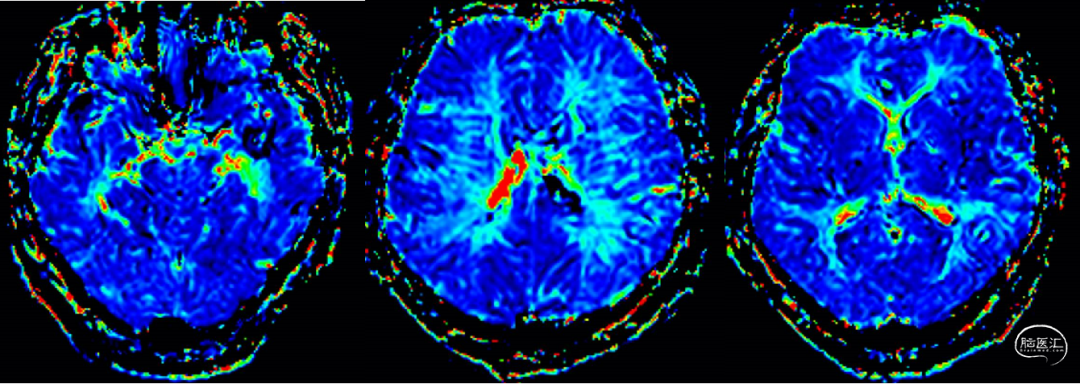

术后磁共振无脑梗及低灌注